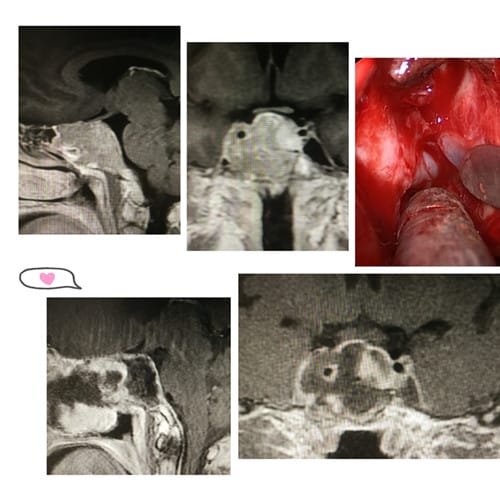

近半年来,43岁的李女士左眼视力缓慢下降,以为是老花眼未予以足够重视,近期,左眼视力直线下降,来到我院眼科就诊,通过颅部核磁共振检查提示李女士的颅底部鞍区有占位,高度怀疑为垂体巨大腺瘤。巨大侵袭性垂体腺瘤,肿瘤最大直径4.7cm,侵袭生长,包绕左侧颈内动脉,并向颅内生长。李女士及家属多方了解北京、上海等地大医院的治疗方案后,了解到我院神经外科内镜切除垂体瘤手术技术成熟,处于省内先进水平,最终决定在我院接受治疗。

“患者在入院前已出现视力视野障碍、头痛等症状,肿瘤最大直径4.7cm,侵袭生长,向两侧完全包绕左侧颈内动脉,knosp分级4级,向上突破鞍隔,往三脑室底下丘脑及脑干前方生长,有脑干受压表现,如果不及时手术患者将有失明的风险”南华大学附属第二医院神经外科王兵博士介绍。为保障手术顺利,医院特邀南昌大学附一医院神经外科主任洪涛教授进行会诊及手术指导,经过专家组综合考虑,决定运用内镜下经鼻入路技术为患者进行手术。

王兵博士为首的专家团队成功实施了手术,患者的侵袭性垂体瘤得到了全切除,术后视力视野改善,无新增神经功能障碍。

王兵博士介绍“该患者的垂体瘤属于向海绵窦侵袭包绕颈内动脉、向鞍上颅内生长的侵犯三脑室底下丘脑的侵袭性垂体腺瘤,被誉为垂体瘤手术皇冠上的明珠,是手术难度最大的一种,手术全切难度大,术后并发症的防控也是难点“。目前,神经外科已经积累了丰富的垂体瘤诊疗经验,发展成为该科的特色,在省内外享有盛名。